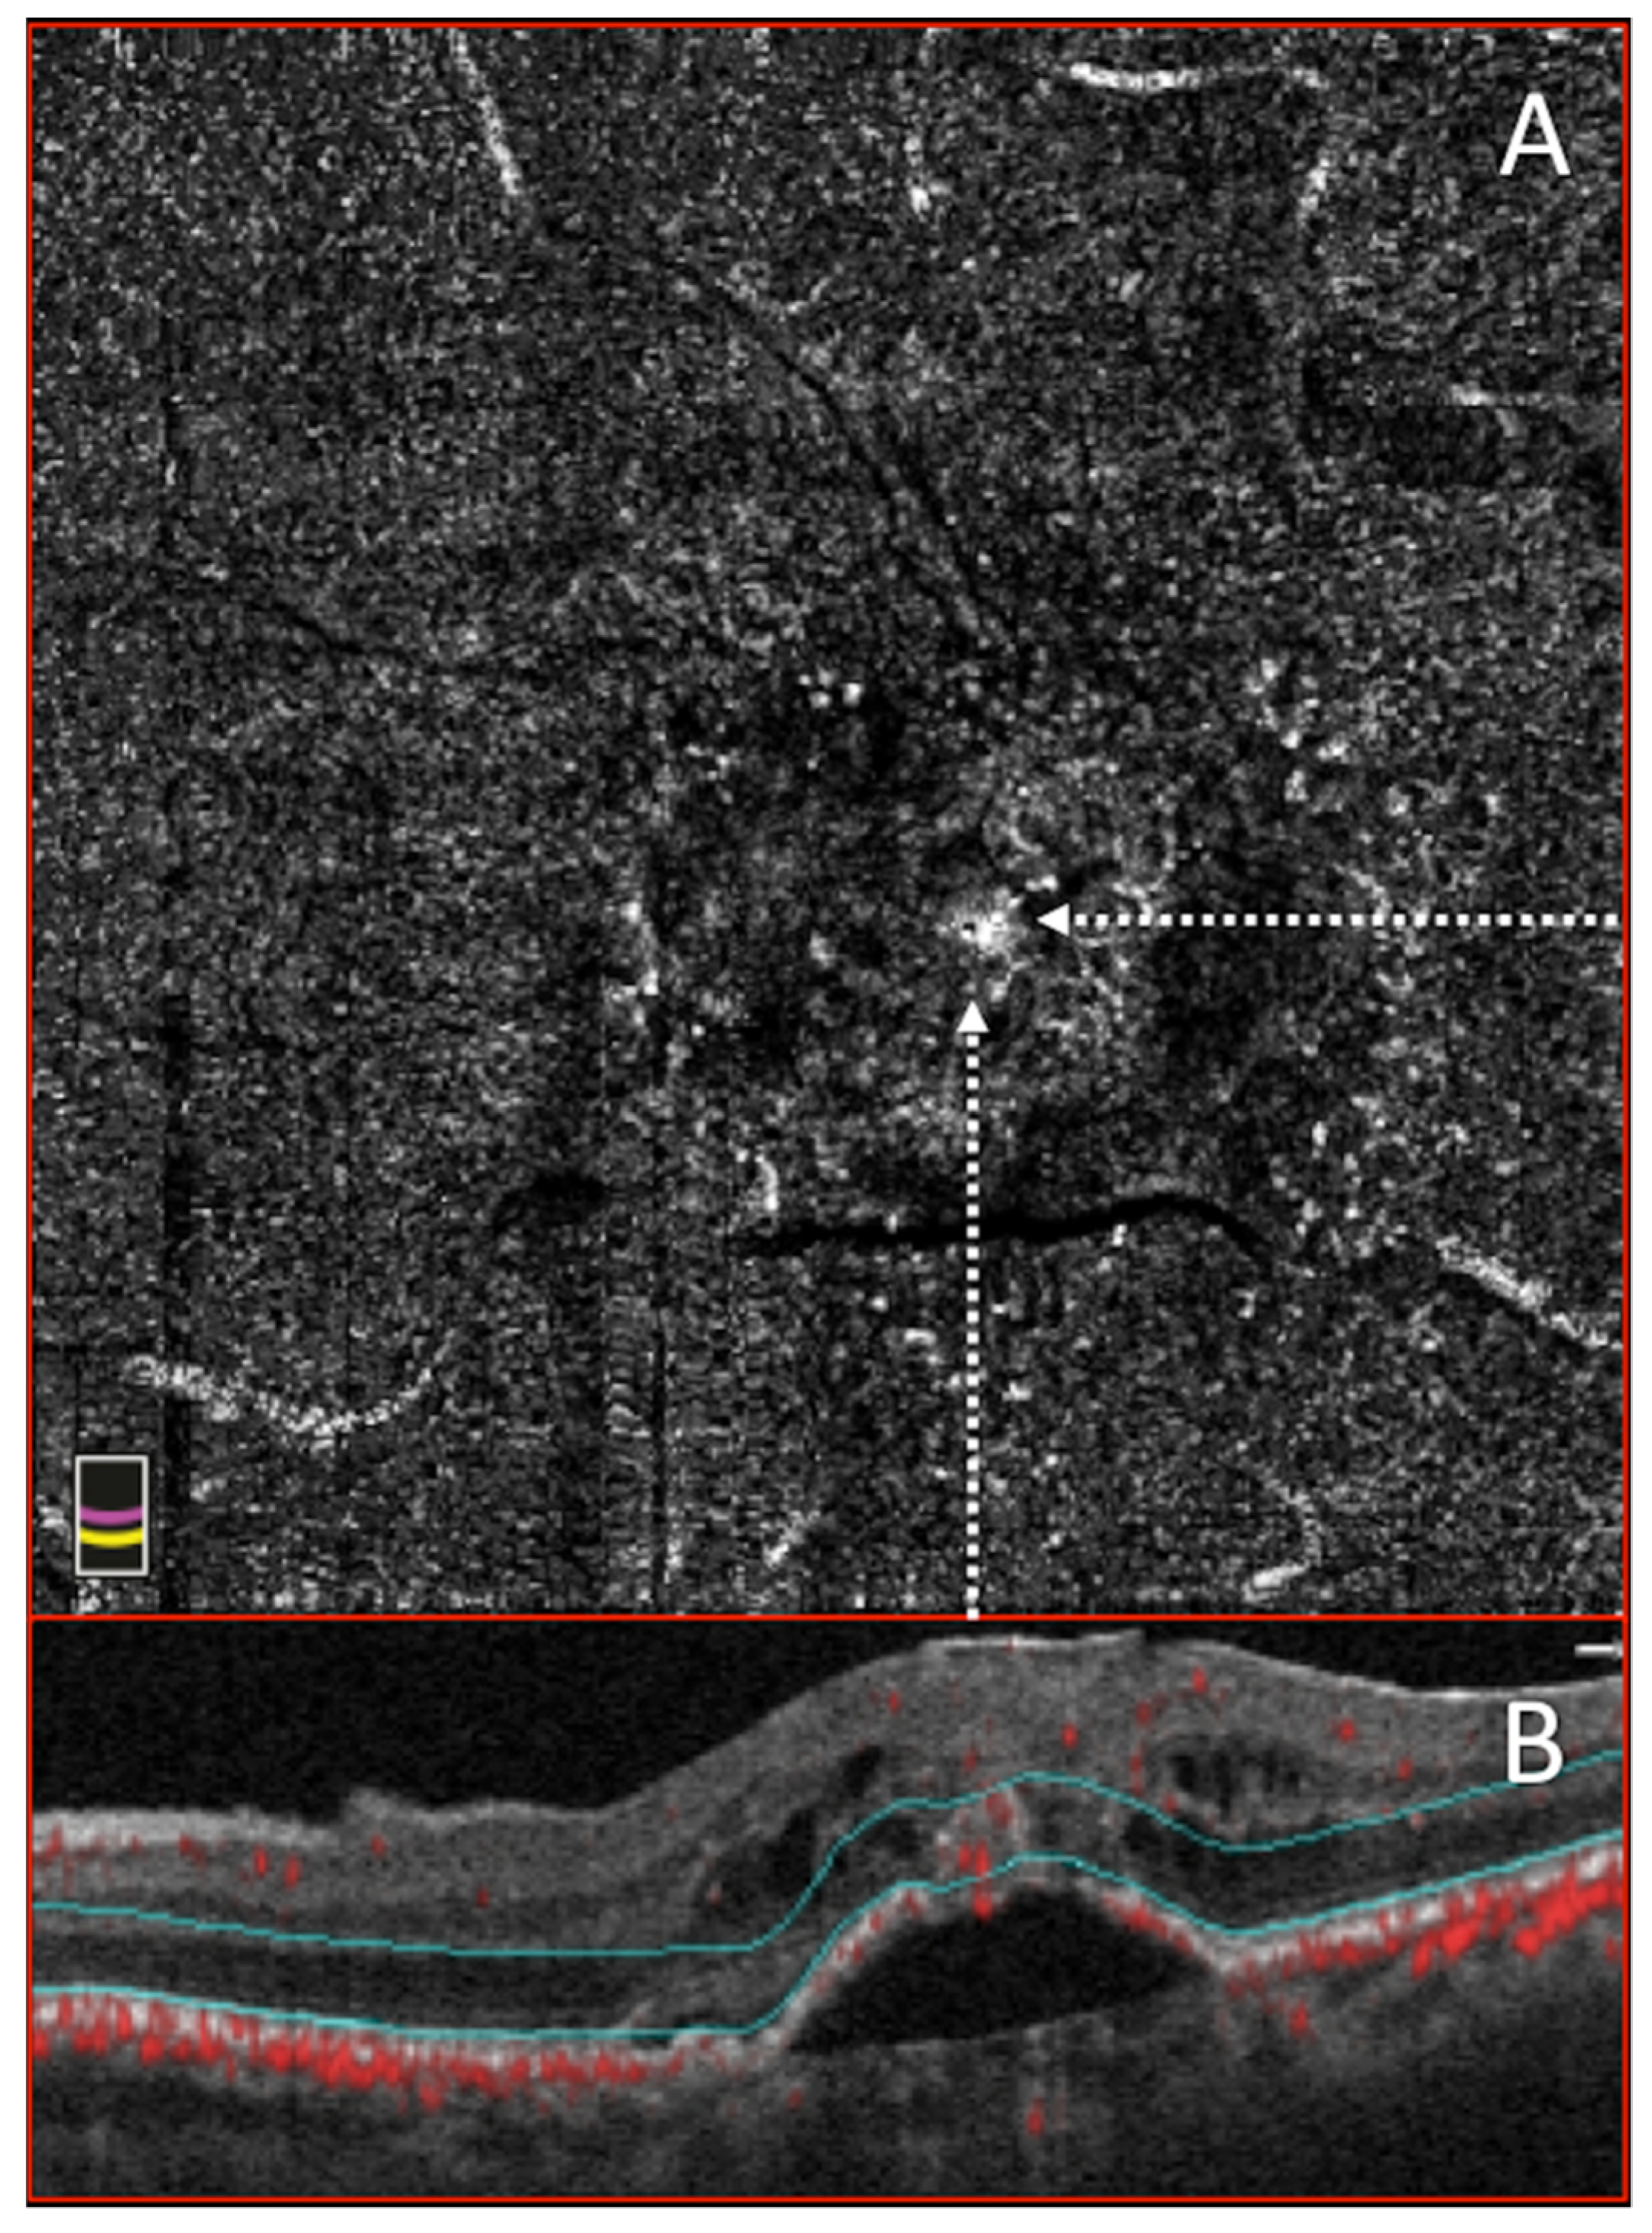

Concerning the diagnosis of type 3 MNV, OCTA has been shown to clearly display the retinal–retinal anastomosis [80]. Such lesions originate from the DCP, creating a clear, tuft-shaped, high-flow network in the outer retinal segment, abutting in the sub-RPE space [84] (Figure 3).

Furthermore, the choriocapillaris segmentation slab could contain a small, clew-like lesion, connected in some cases with the choroid through a small-caliber vessel [84,85,86].